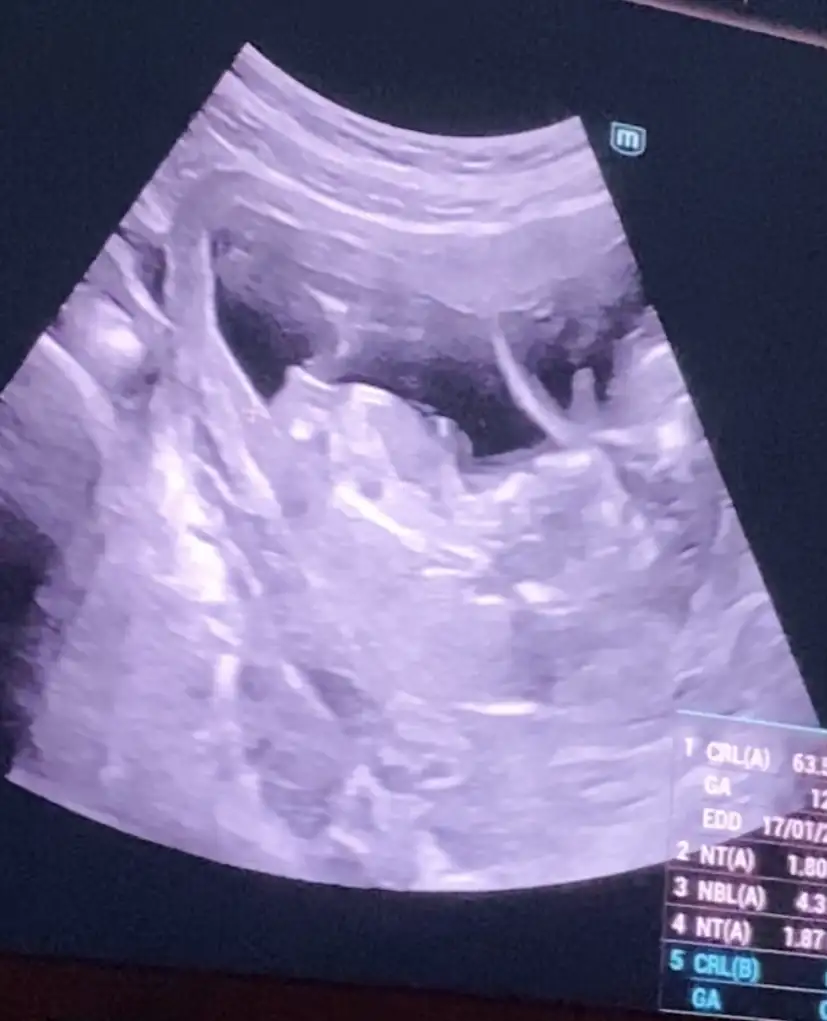

Kızlar cinsiyet tahminininiz nedir tecrübeliler yorum yapabilirim diğer bebek kızmış doktor ikinci bebekten emin olamadı yüzde 60 kız dedi